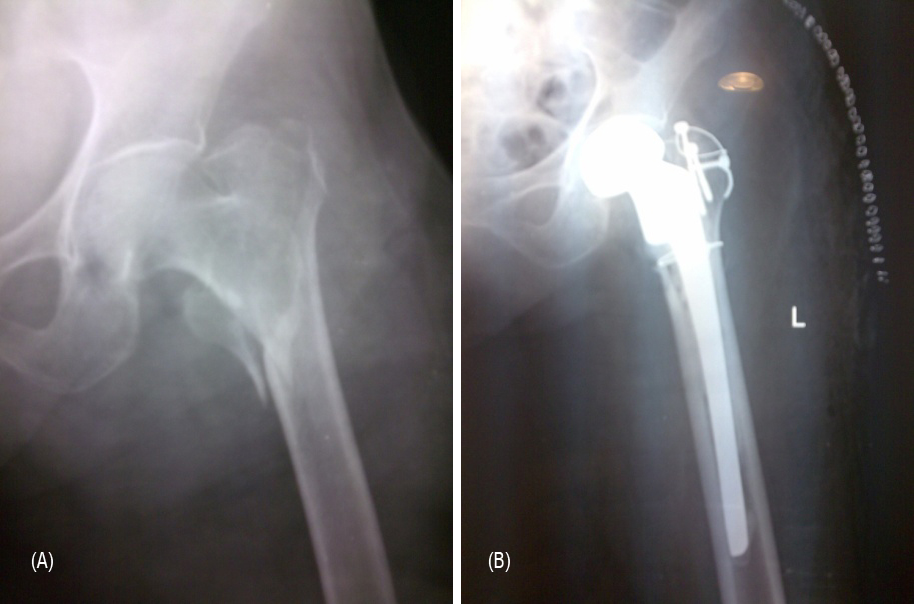

From day one, in-bed exercises and mobility are advocated, to prevent complications like DVT, bed sores and pneumonia. Next day, out of bed mobility with the help of a walker is allowed with weight bearing as tolerated. On day three, wound dressings are changed and discharge planned based on patients comfort and mobility, usually on day 4 or 5 (Figures 5A, 5B, 6A and 6B).

Figure 5: (A) Comminuted IT fracture. (B) Post operative radiograph.